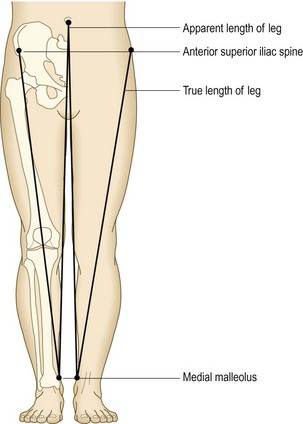

Shortening: Shortening occurs in hip and other lower limb conditions (Box 14.24). Apparent shortening is present if the affected limb appears shortened, usually because of an adduction or flexion deformity at the hip.